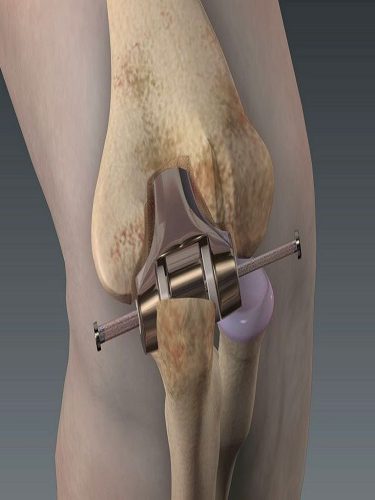

– OVER KİST AMELİYATI (YUMURTALIK KİSTİ AMELİYATI) (OVER KİSTEKTOMİ) Hemen her kadında hayatını belirli bir döneminde over kistlere rastlanabilmektedir. Bu kistlerin farklı tüpleri bulunmaktadır. Bu çeşitliliğe uygun tedavi yöntemleri de bulunmaktadır. Over kistlerinde en sık rastlanan şikayetler cinsel ilişki sırasında ağrı, kasık ağrısı, karında şişkinlik veya basınç hissi ve adet düzensizlikleridir. Yumurtalık (over) kistleri her…